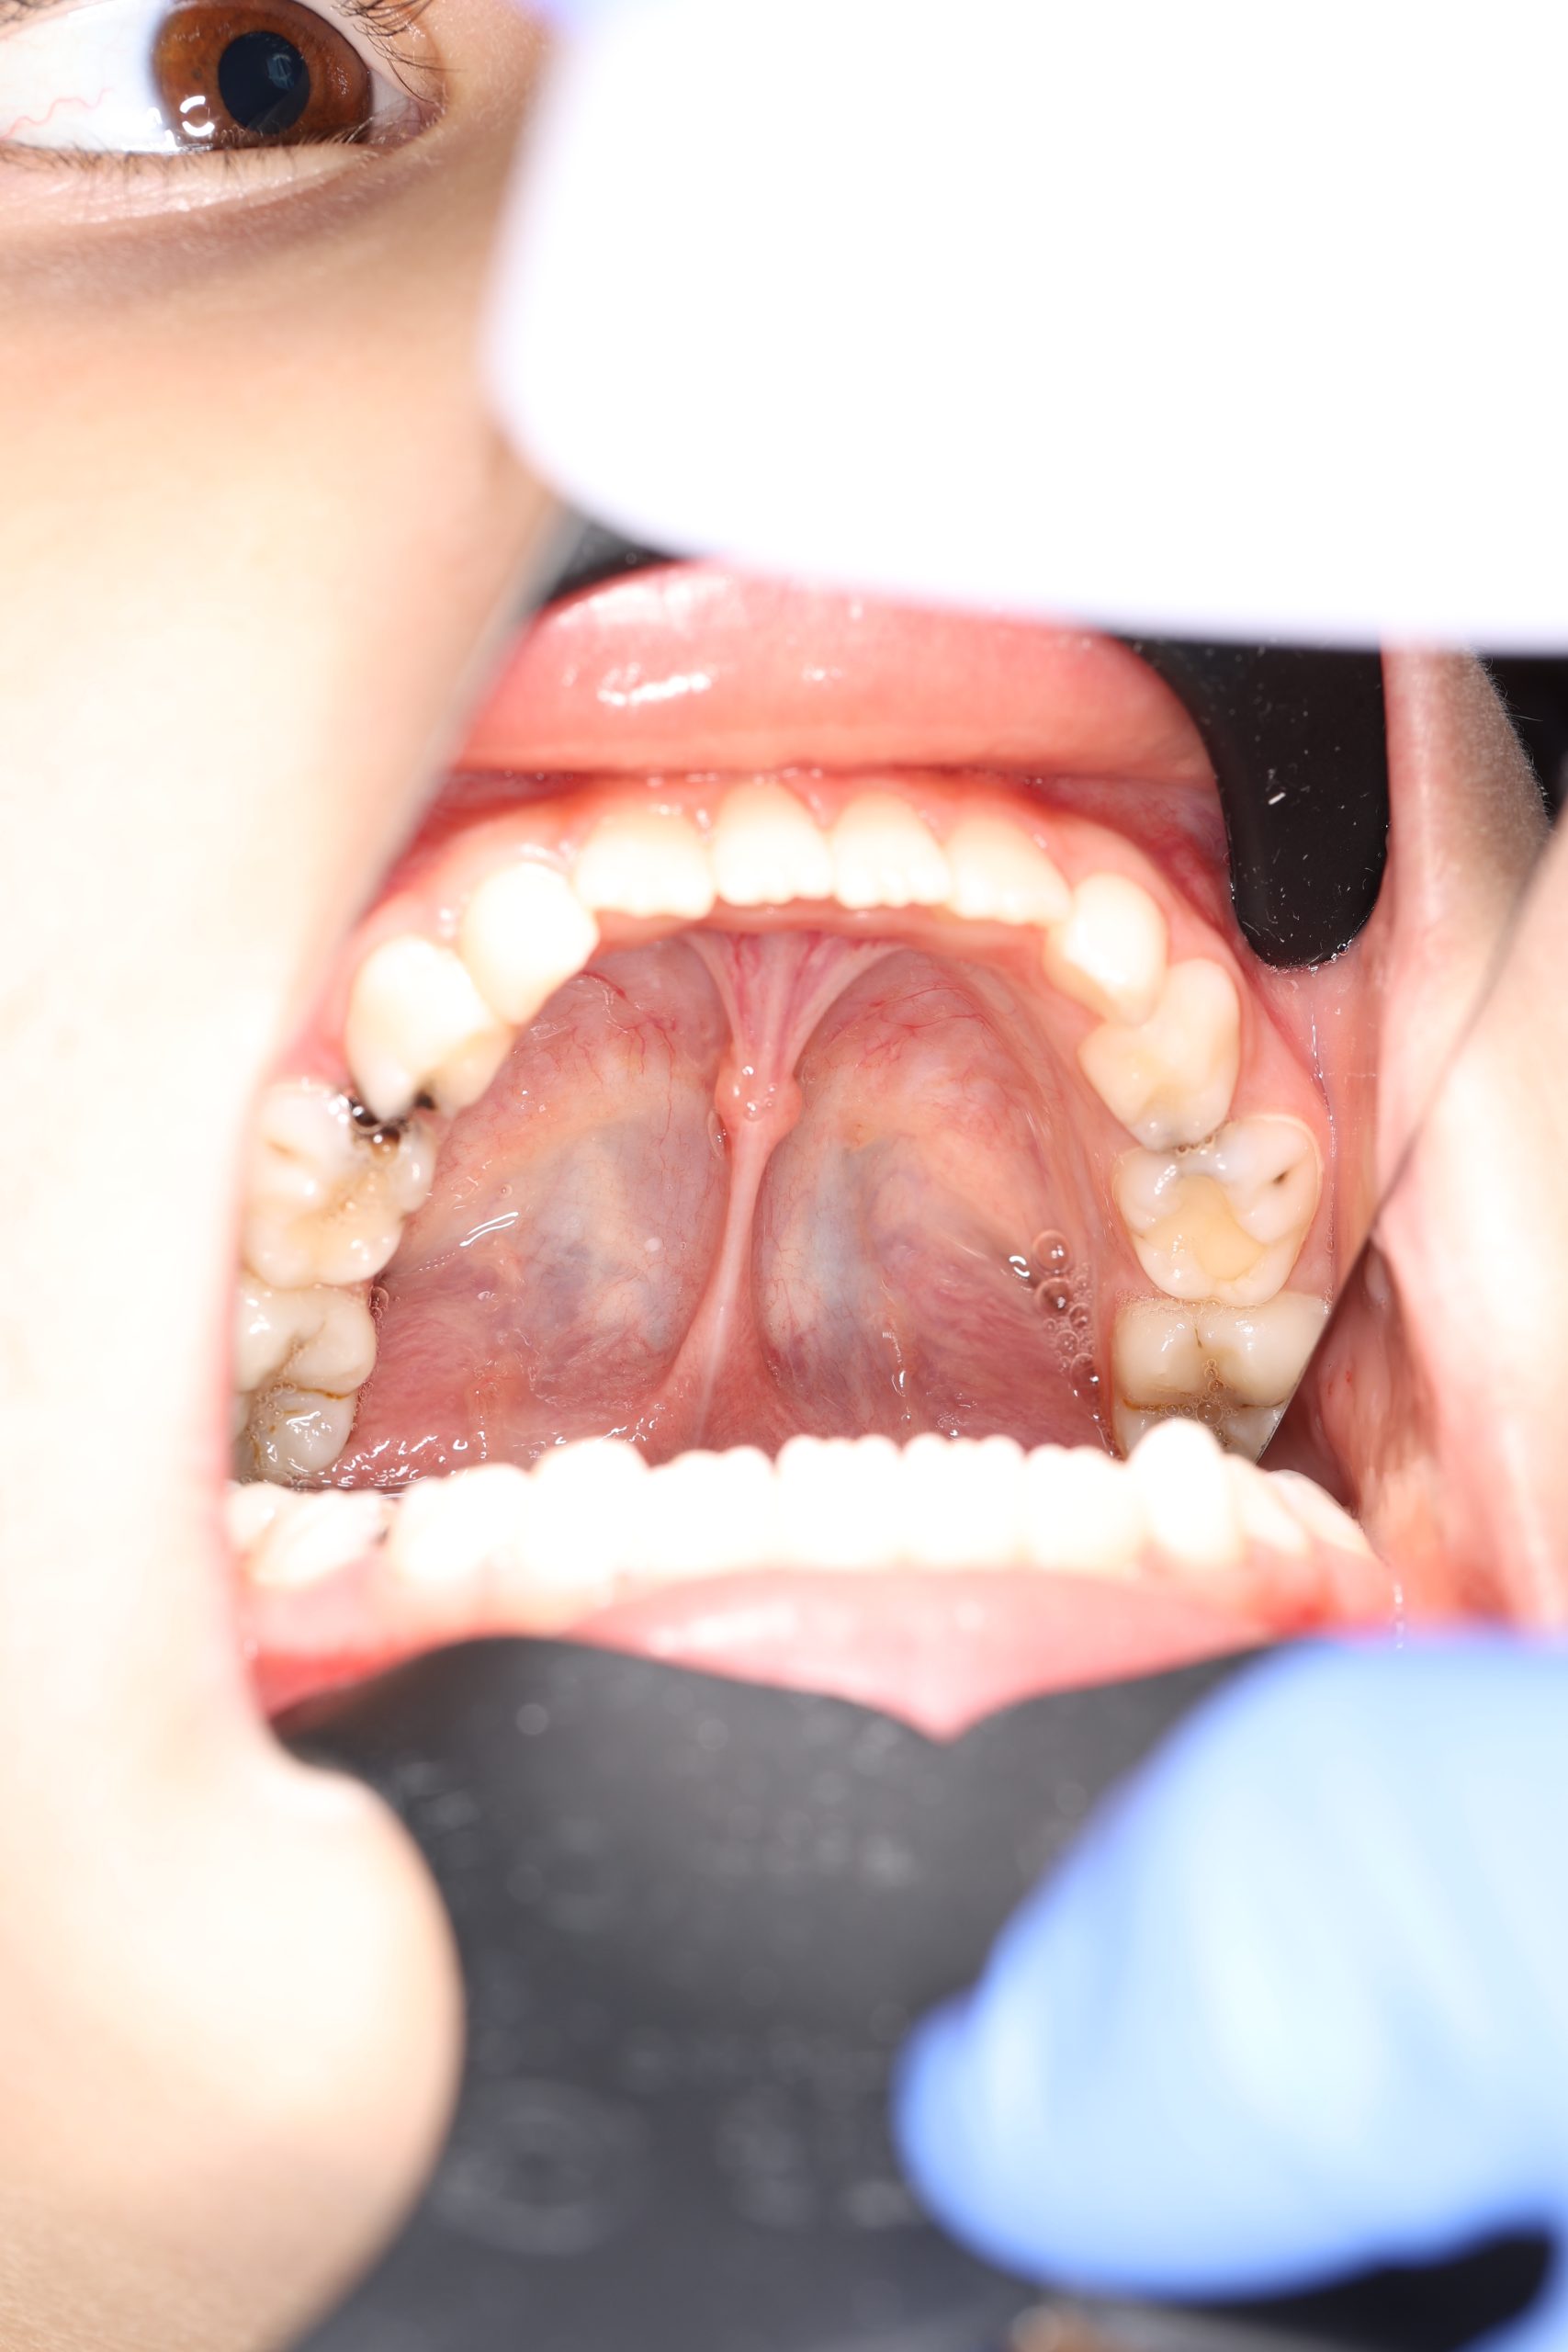

- There’s too much damage from decay for a simple filling to hold

- There’s a structural defect in the enamel (due to developmental issues)

Stainless Steel Crowns (SSC)

The most popular type for back baby teeth. Durable, cost-effective, and fast to place, they provide excellent protection against further decay.